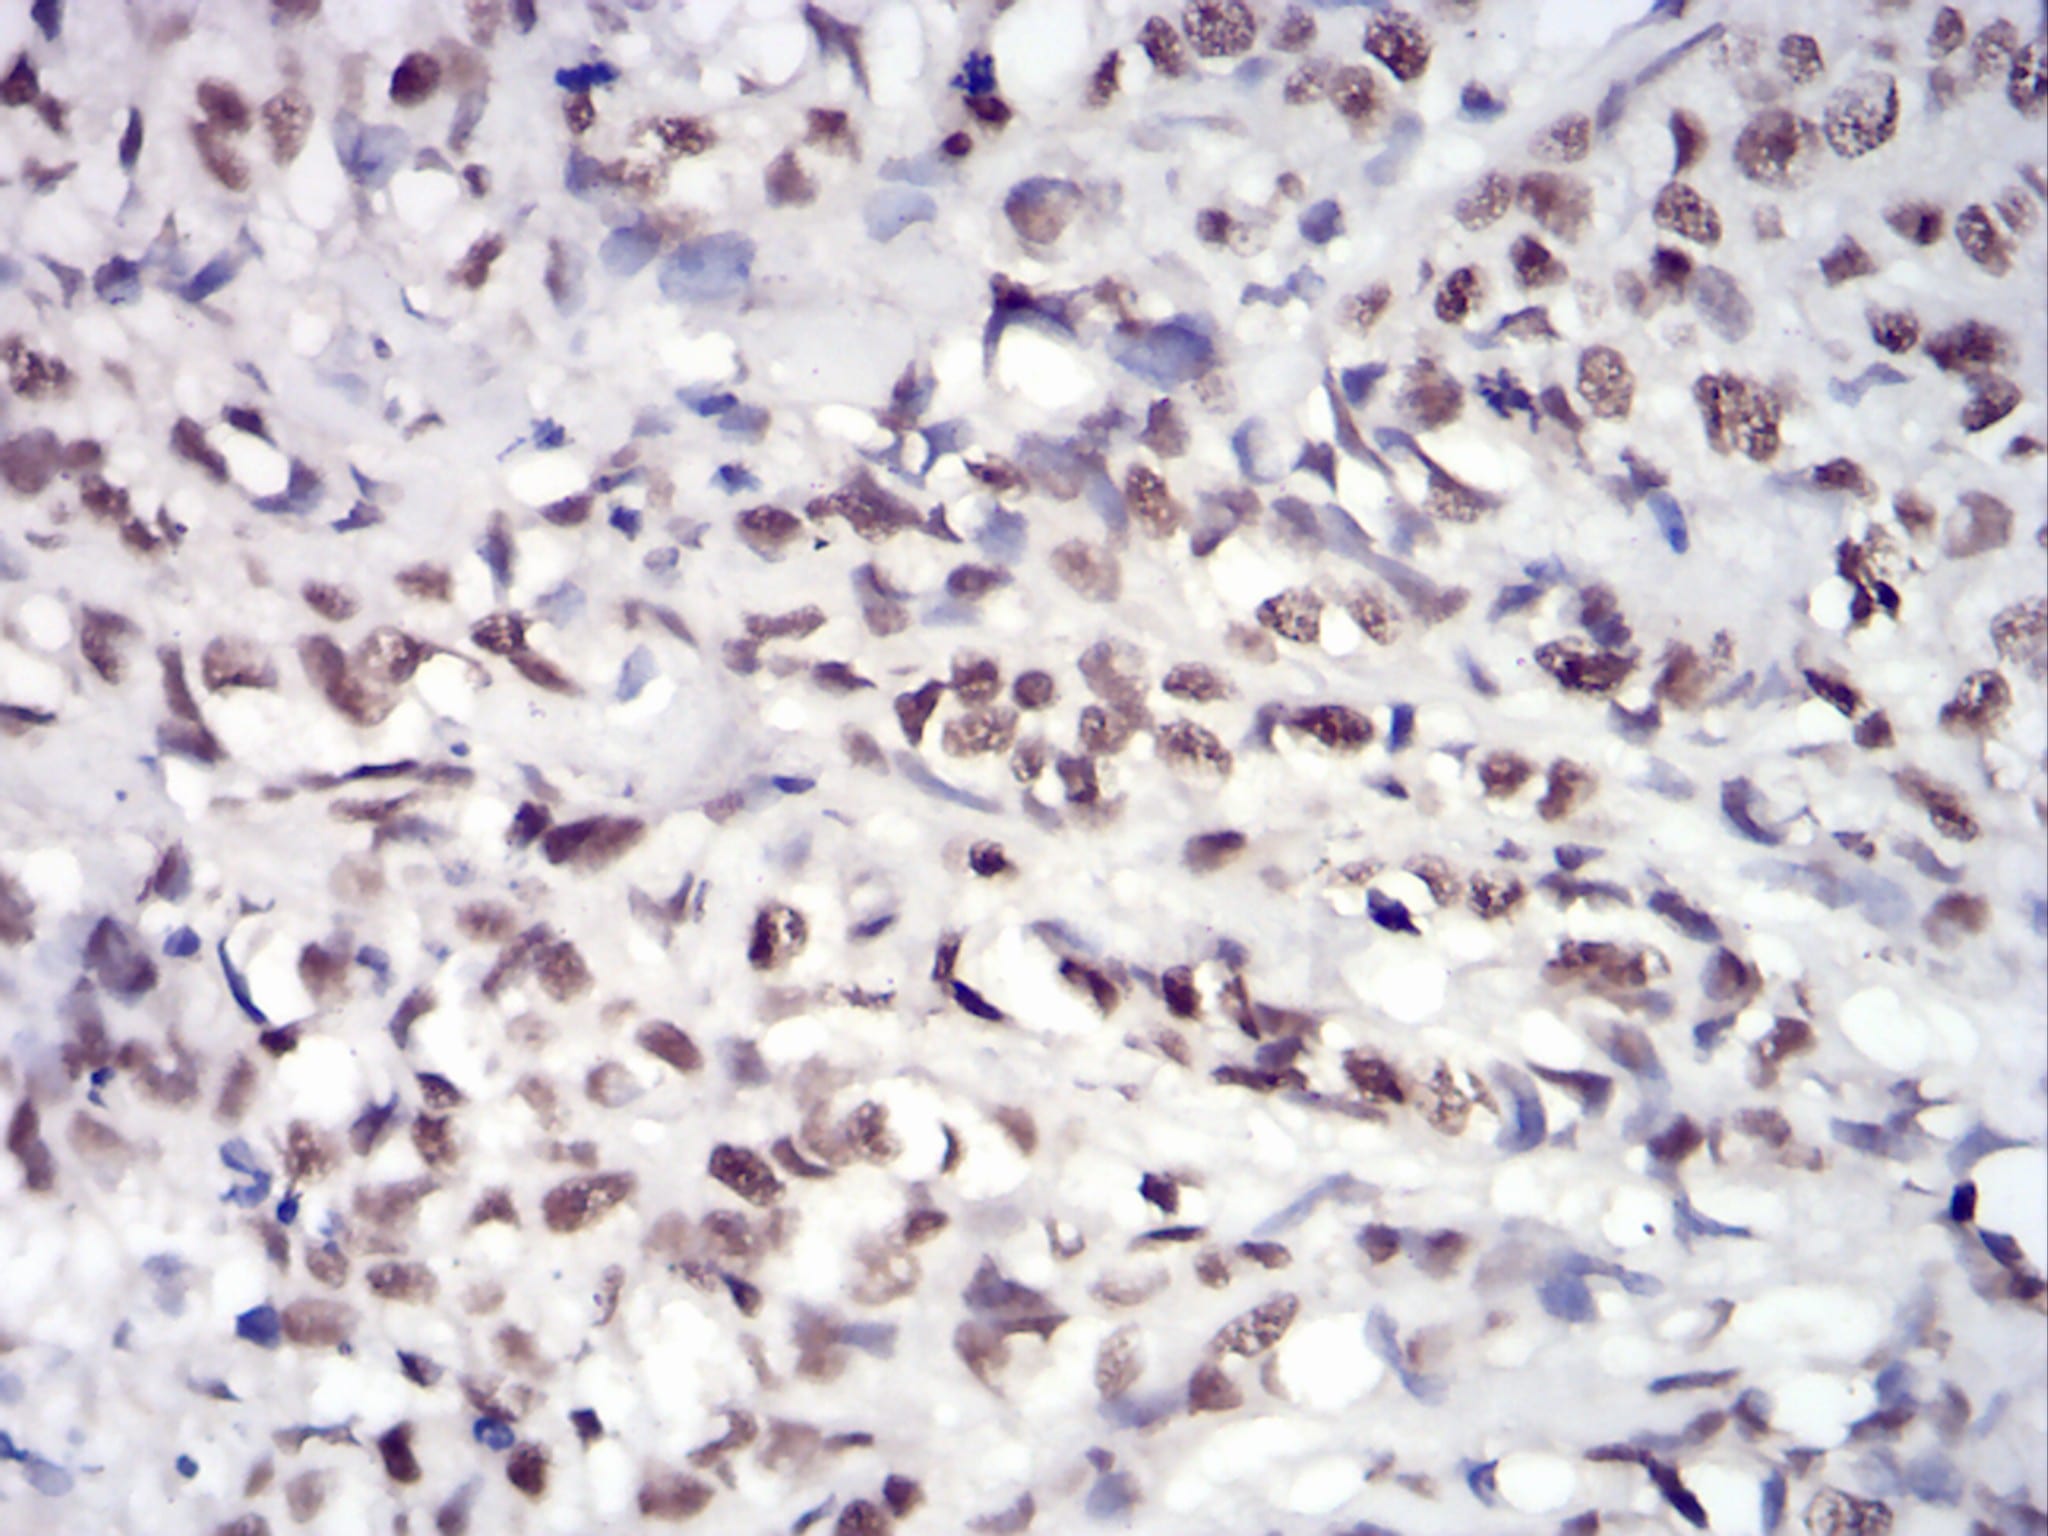

分类: 科研抗体货号: 30744别名: EIF-5A; EIF5A1; eIF5AI应用: IHC,FCM反应种属: Human